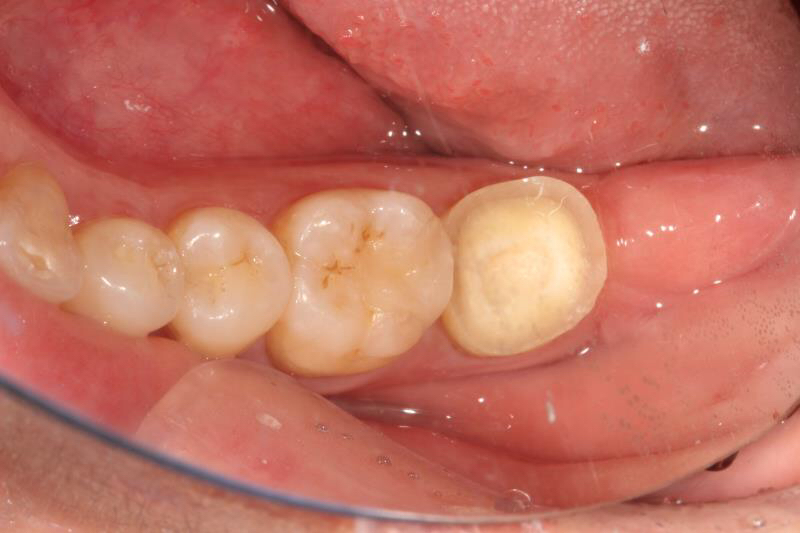

今天给大家分享的病例是一位中年女性,17缺失,由于长时间未修复,47伸长,留给17修复的空间不足。

老卢给她的治疗方案是:17种植修复,47根管治疗后截冠、高嵌体修复。这样可以最大限度的增加患者的咀嚼效率。

由于患者喉反射比较严重,种植牙冠和高嵌体都是用我们德国进口CEREC扫描制做的哦,与传统取模相比大大降低了不适感。